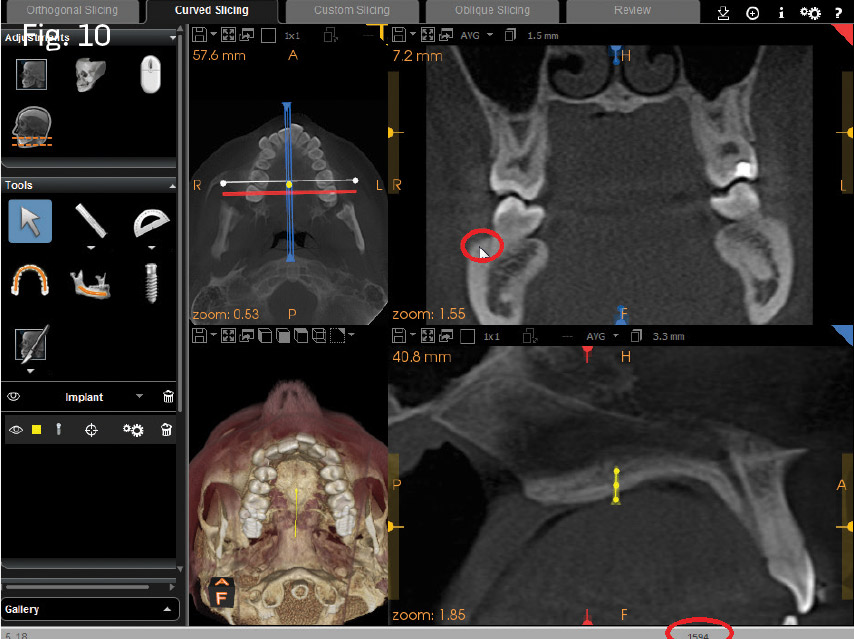

Using CS 3D Imaging simulation software, I hovered the mouse pointer over the buccal shelf of the mandible, as well as the anterior palate, approximately 13mm from the gingival margin of the upper incisors, and observed the relative density value in the lower-right corner of the screen (Figs. 10 and 11). I made note of the values of these individual locations. The buccal shelf represents probably the most dense area of bone for the individual patient in the maxillomandibular complex. The anterior palate and just off the midline allows for assessment of palatal bone values relative to the buccal shelf. With both of these comparisons in mind, I assessed the possible insertion sites at the direct midpalatal suture at the midmesio/distal of the upper first molars, versus the adjacent paramedian locations from the simulated insertion. I made a decision whether to insert a single miniscrew for molar intrusion, instead of two miniscrews at the adjacent paramedian locations.

In Case 1, a collimated CBCT view of the maxilla was captured with a Carestream Dental CS 9300. A miniscrew placement simulation was performed, showing excellent bone density at the midpalatal suture, allowing for a single miniscrew and dumbbell (see Fig. 4). In Case 2, a similar simulation was also performed; both quality and quantity of bone were assessed. It was determined that a single midpalatal miniscrew at the midpoint of the suture would be less reliable than two paramedian miniscrews. The density-gradient tools of the miniscrew placement simulation showed an acceptable gradient of relative bone density in two paramedian locations, rather than a single screw placed in the midpalate.